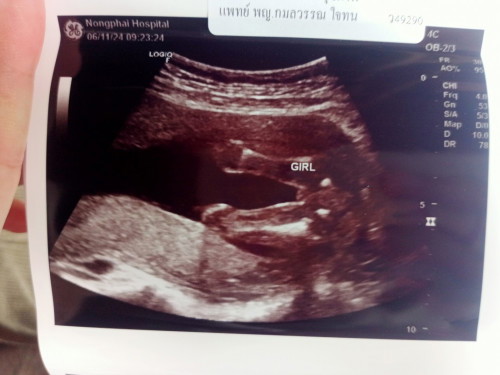

วันนี้โรงพยาบาลโทรมาแจ้งผลเจาะเลือดตรวจดาวน์ซินโดรม ผลออกมาคือเสี่ยงสูงค่ะ 1:120 หมอจะนัดเจาะน้ำคร่ำ วันที่ 7 พฤศจิกายนนี้ค่ะ ตอนนี้แม่เครียดมากค่ะ คิดมาก ร้องไห้ กลัวไปหมด แม่ไม่ได้กลัวที่จะต้องเจาะน้ำคร่ำนะคะ กลัวลูกเป็นอะไรมากกว่า มีแม่ๆคนไหน ผลเลือดเสี่ยงสูง แล้วลูกออกมาปกติบ้างไหมคะ ตอนนี้เครียดมาก #เจาะน้ำคร่ำ #เจาะดาวน์ซินโดรม